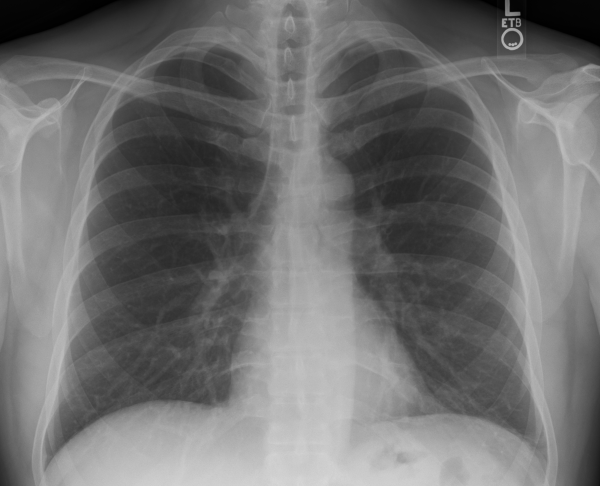

Житель Йошкар-Олы лечился в Советской ЦРБ. У мужчины был лабораторно подтвержден коронавирус. Течение болезни осложнилось тотальной пневмонией и сердечно-легочной недостаточностью.